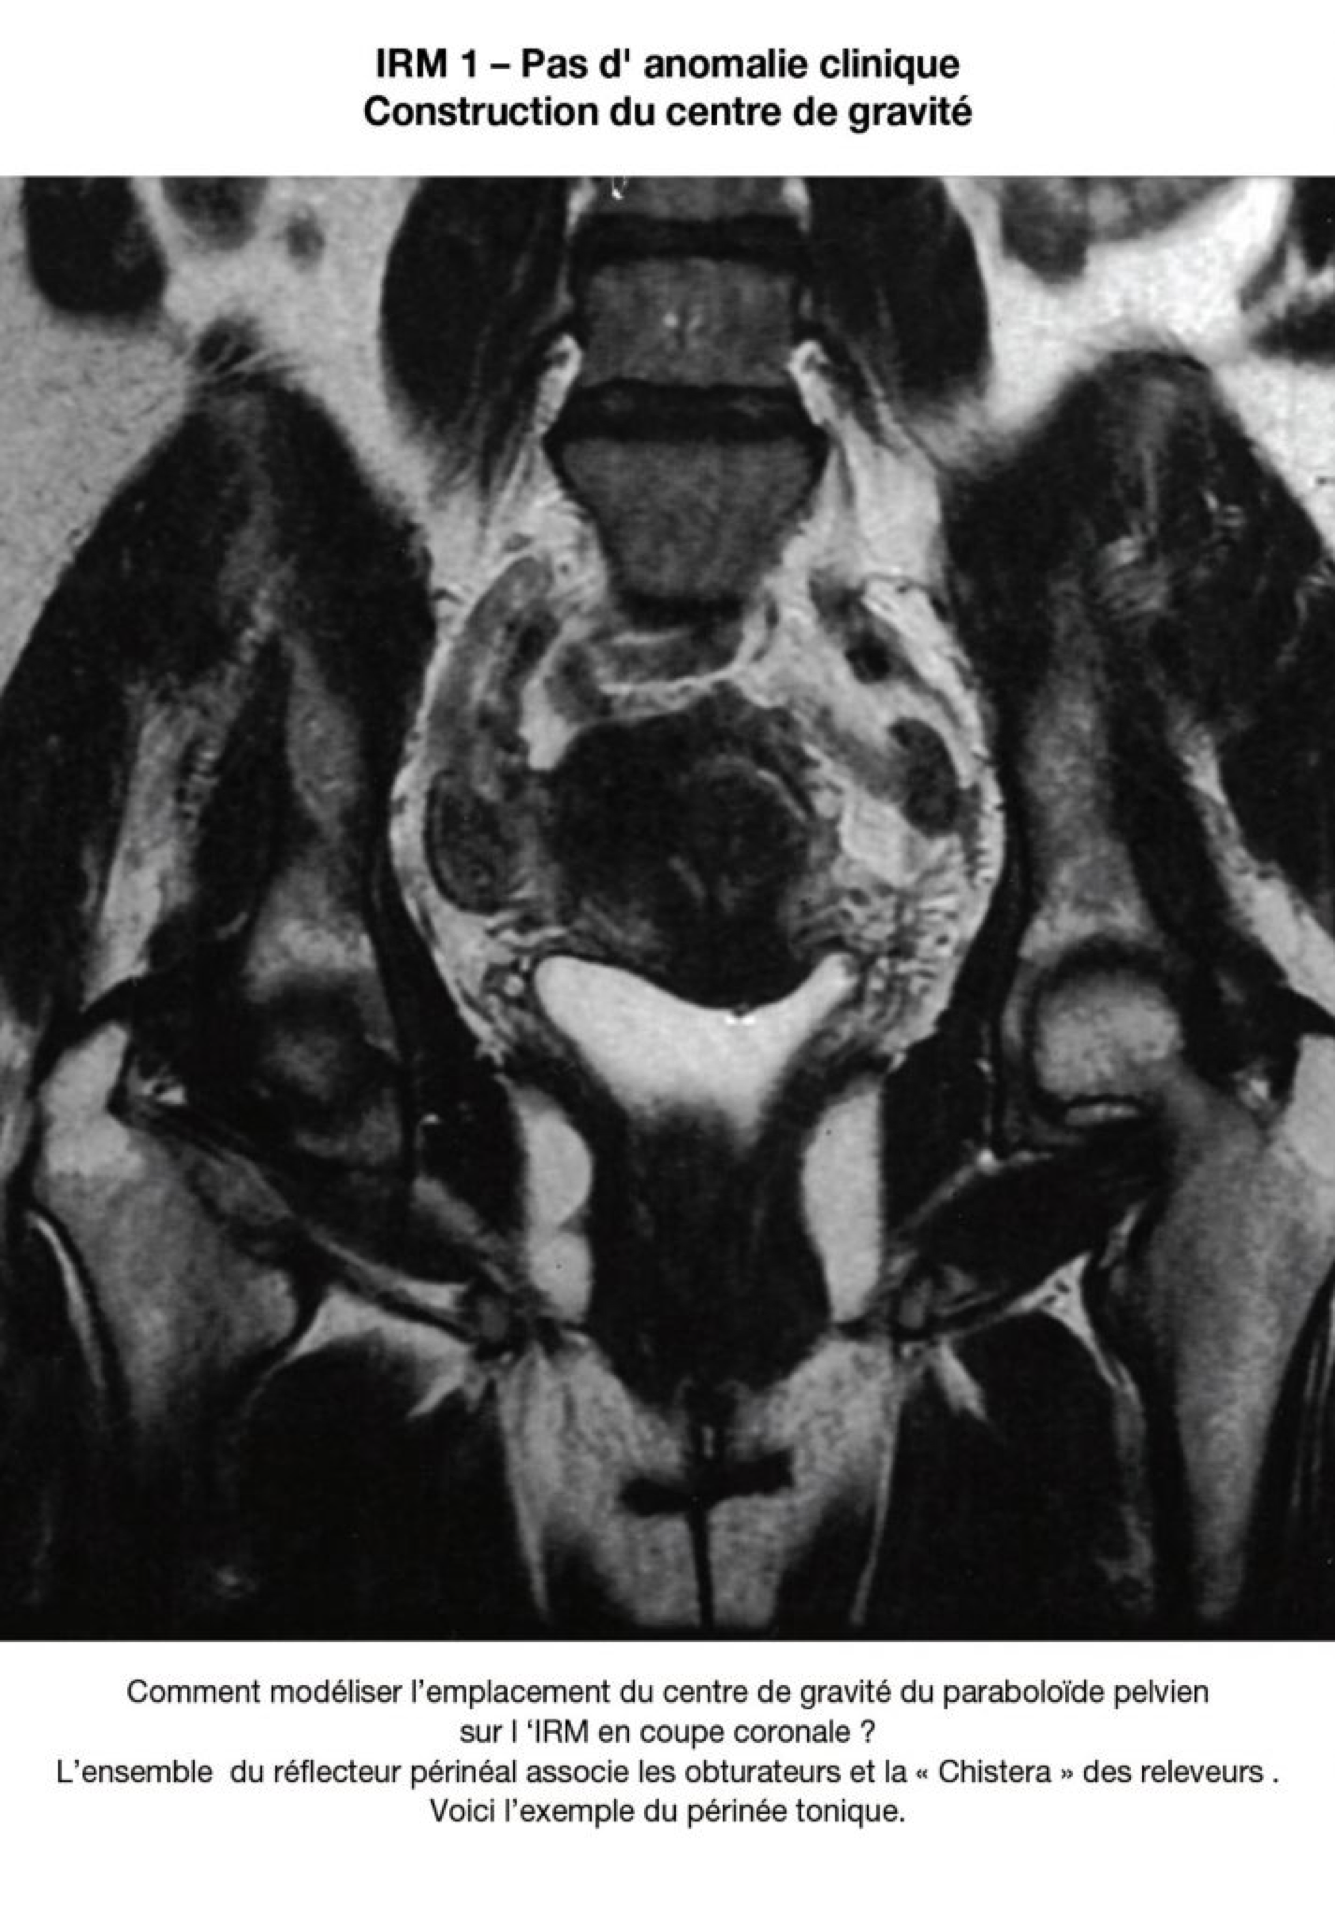

Pour que le principe puisse trouver une application clinique, il faut pouvoir dessiner, ou modéliser les vecteurs de pression. La première étape est de déterminer la position du centre de gravité de cette pseudo parabole.

Le centre de gravité n’est pas au centre d'un cercle, car les parois ne sont pas régulières. La parabole a la forme d’une poire inversée. Son centre de gravité se trouve plus ou moins haut, selon que la poire est plus ou mois allongée. Le vecteur des pressions qui s’appliquent dans le petit bassin passera par le centre de gravité du plan de la parabole (centre) ou du paraboloïde (excentré).

La position du centre de gravité du plan de réflexion dépends en arrière de la forme du sacrum (plat, concave, court, long...) et sur les côtés, de la forme (variable) des parois latérales (muscles obturateurs internes et muscles releveurs).

La forme des repères osseux est immuable. Les limites des parties molles, elles, sont variables. Les parties molles ne se limitent pas au plancher pelvien, elles incluent les obturateurs internes .La variation de volume des obturateurs va faire varier la position du centre de gravité du paraboloïde.

Le « vecteur résultant » des forces gravitationnelles et abdominales va être renvoyé plus ou moins haut, plus ou moins bas, selon que ces muscles seront épais (femme jeune - centre de gravité élevé), ou seront atrophiques ou délabrés (centre de gravité abaissé).

La première étape serait la modélisation matricielle du centre de gravité sur une coupe coronale, c’est à dire proche du plan de réflexion du paraboloïde. La deuxième étape serait la construction du plan de réflexion du paraboloïde pelvien. Le programme établit la direction du vecteur réfléchit, selon les lois physiques de la parabole : le point d'application de la pression abdominale passe par le centre de gravité qui a été reconnu. - Le repositionnement chirurgical sera t il possible sans déséquilibrer le pelvis ?